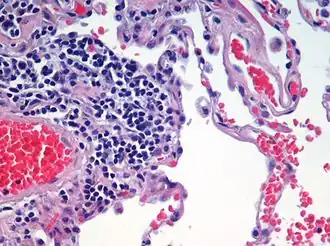

Vedere microscopică a unui specimen histologic de țesut uman plămân colorat cu hematoxilină și eozină.

Țesutul reprezintă o grupare de celule interconectate, care au aceeași origine, formă și structură și îndeplinesc aceeași funcție. Mai multe țesuturi formează un organ. Mai multe organe formează sisteme de organe, iar totalitatea sistemelor de organe formează organismul. Știința care se ocupă cu studiul țesuturilor se numește histologie.